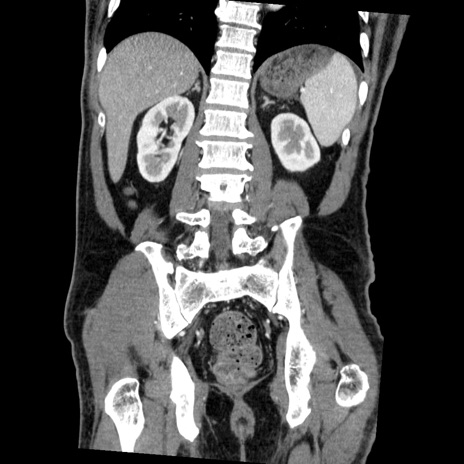

症例22(冠状断像)

【症例】50歳代男性

【主訴】腹痛

【現病歴】AVMからの被殻出血のため回復期リハ病棟入院中。 本日午後3時頃急に下腹部痛が出現した。

【既往歴】AVM、被殻出血、虫垂炎、高血圧

【身体所見】意識晴明、左半身不全麻痺、会話の理解は良好、36.5°C、腹部:膨隆、全体に板状硬、下腹部正中に圧痛点あり、反跳痛-、筋性防御不明、右下腹部にope scar

【データ】WBC 9400、CRP 0.06